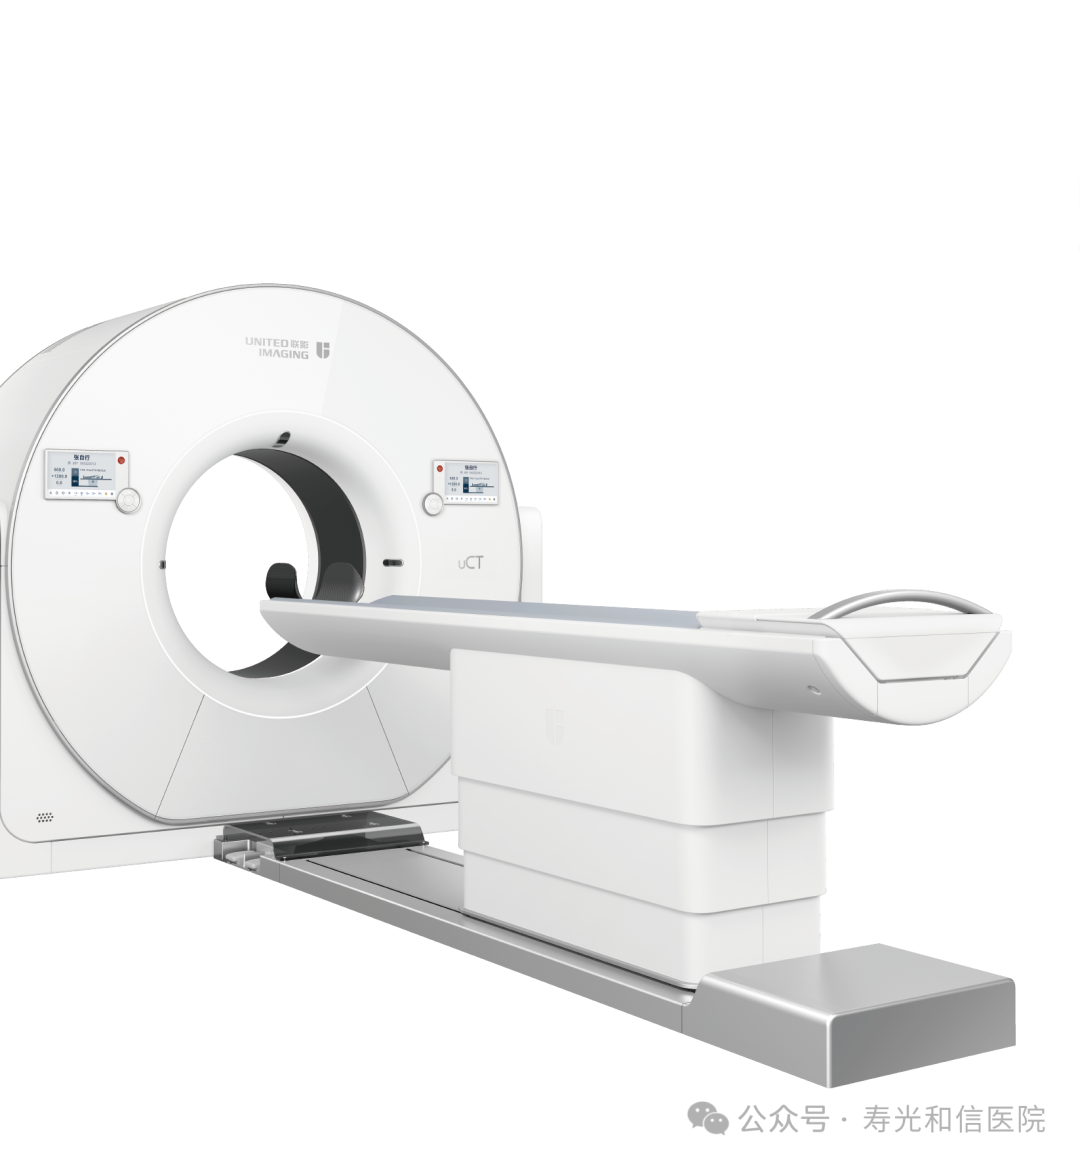

320排!640层!0.25秒一圈!新CT真硬核

联影640层CT是中国CT届的“天花板”,集当今CT领域的顶尖科技于一身,将各项临床应用发挥到极致,为患者带来精准、舒适、安全的CT检查新体验。建立了心血管、神经、肿瘤、呼吸系统、泌尿系统及骨科专业等疾病的成像和低剂量筛查领域全新标准,真正实现全方位成像,结合AI人工智能技术,提高疾病诊断率。